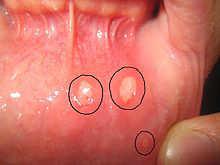

The aphthas treatment can have different lasers applications. In the upper case, the aphthas surface was removed with pulsed setting, while the case 1 and 3 the aphtha was dried up with without touch.